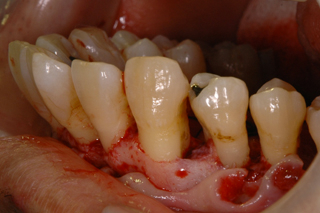

歯肉を切開し骨をあらわにしたところ、最奥歯の骨の欠損が確認できます。

AFTER ( 術中・術後 )

※血が苦手な方に配慮して画像の色味を修正しています。

欠損部にエムドゲイン、周囲から採取した骨を填塞し、その上に膜(バリアメンブレン)を設置しています。

この方の場合は手前の歯のすり減り等を考慮すると歯ぎしりなどの噛む力のコントロールがなされていない、または噛み合わせが悪く現状に至ったと推察しました。

基本治療から3ヵ月しても改善が見られなかったため再生療法を施術し現在も加療中です。